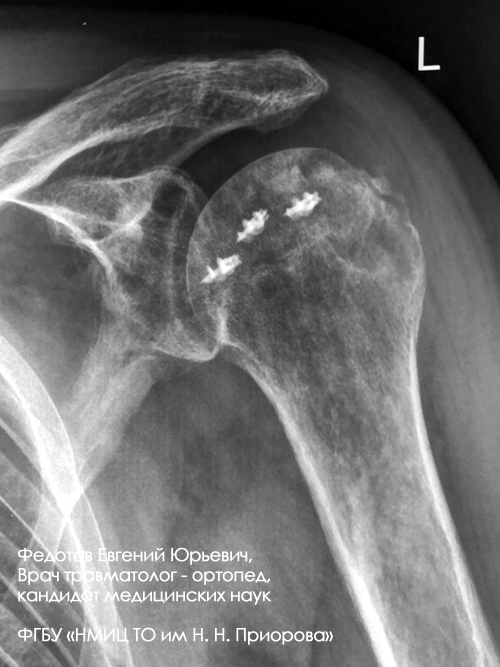

Перелом большого бугорка плечевой кости

Операция: Открытая репозиция, анкерная фиксация большого бугорка плечевой кости.

Неправильно срастающийся оскольчатый перелом большого бугорка плечевой кости.

Операция: Открытая репозиция большого бугорка плечевой кости с фиксацией анкерным швом